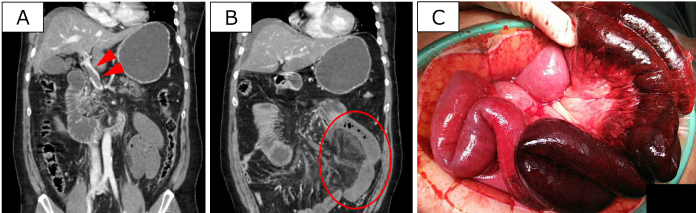

Superior mesenteric vein thrombosis (SMVT) is a rare condition characterized by thrombus formation in the superior mesenteric vein. SMVT is generally caused by abnormal blood coagulation, inflammation, or surgical interventions. This condition can lead to intestinal ischemia and necrosis due to blood flow stasis. We report the case of a man in his 60s who presented with abdominal pain and vomiting. Abdominal contrast-enhanced computed tomography shows a thrombus in the portal and superior mesenteric veins, and reduced contrast in the small intestine. Approximately 1.5 m of the necrotic jejunum was resected, an open management approach was undertaken, and anticoagulation with continuous intravenous heparin was initiated. On the fourth day of treatment, a thrombus was retrieved from the superior mesenteric vein within the main trunk of the portal vein using a stent clot retrieval device. The patient's bowel edema improved soon thereafter. This case of SMVT was successfully managed using a hybrid approach of bowel resection and transcatheter thrombus retrieval.